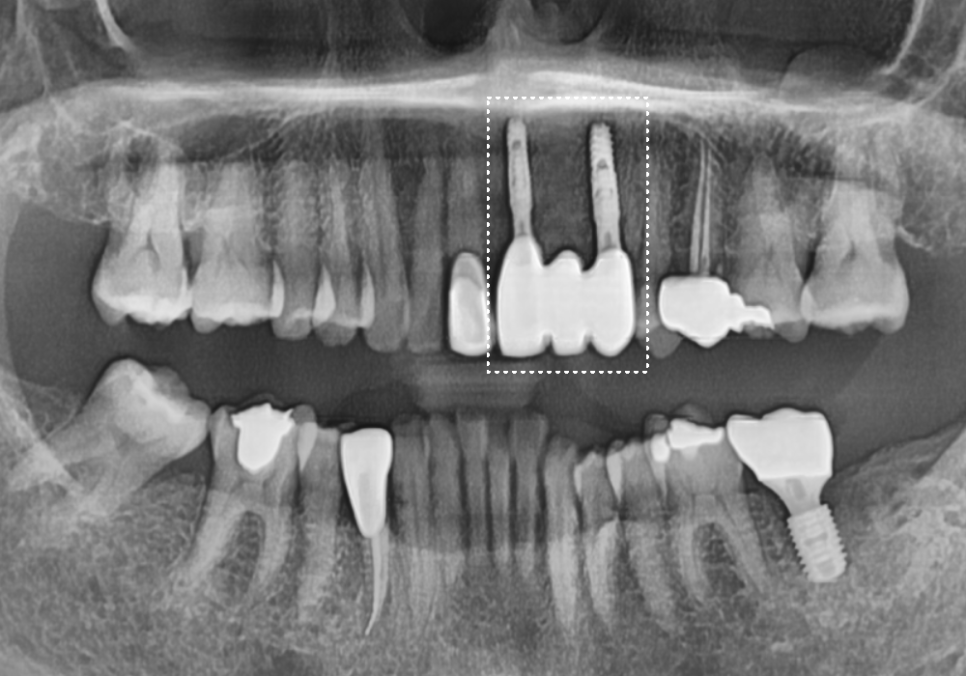

방사선 사진을 살펴보니 역시나,

2차 충치로 인해 치아 뿌리와 보철물 사이가

완전히 끊어져있네요.. ㅜㅜ

하지만 이 환자분은

가운데 앞니 씌운 곳(#21)이

뿌리 쪽까지 염증이 퍼져 있는 상태였어요.

오래된 앞니 크라운 냄새, '이것' 때문일 수 있습니다.

이 상태로 신경치료를 하고 다시 씌운다 해도,

얼마 못 가 다시 문제가 생겨

오래 사용하지 못할 가능성이 높기 때문에..!

안타깝지만..환자분의 장기적인 치아 건강을 위해

발치 후 임플란트로 진행하실 것을 권해드렸습니다.